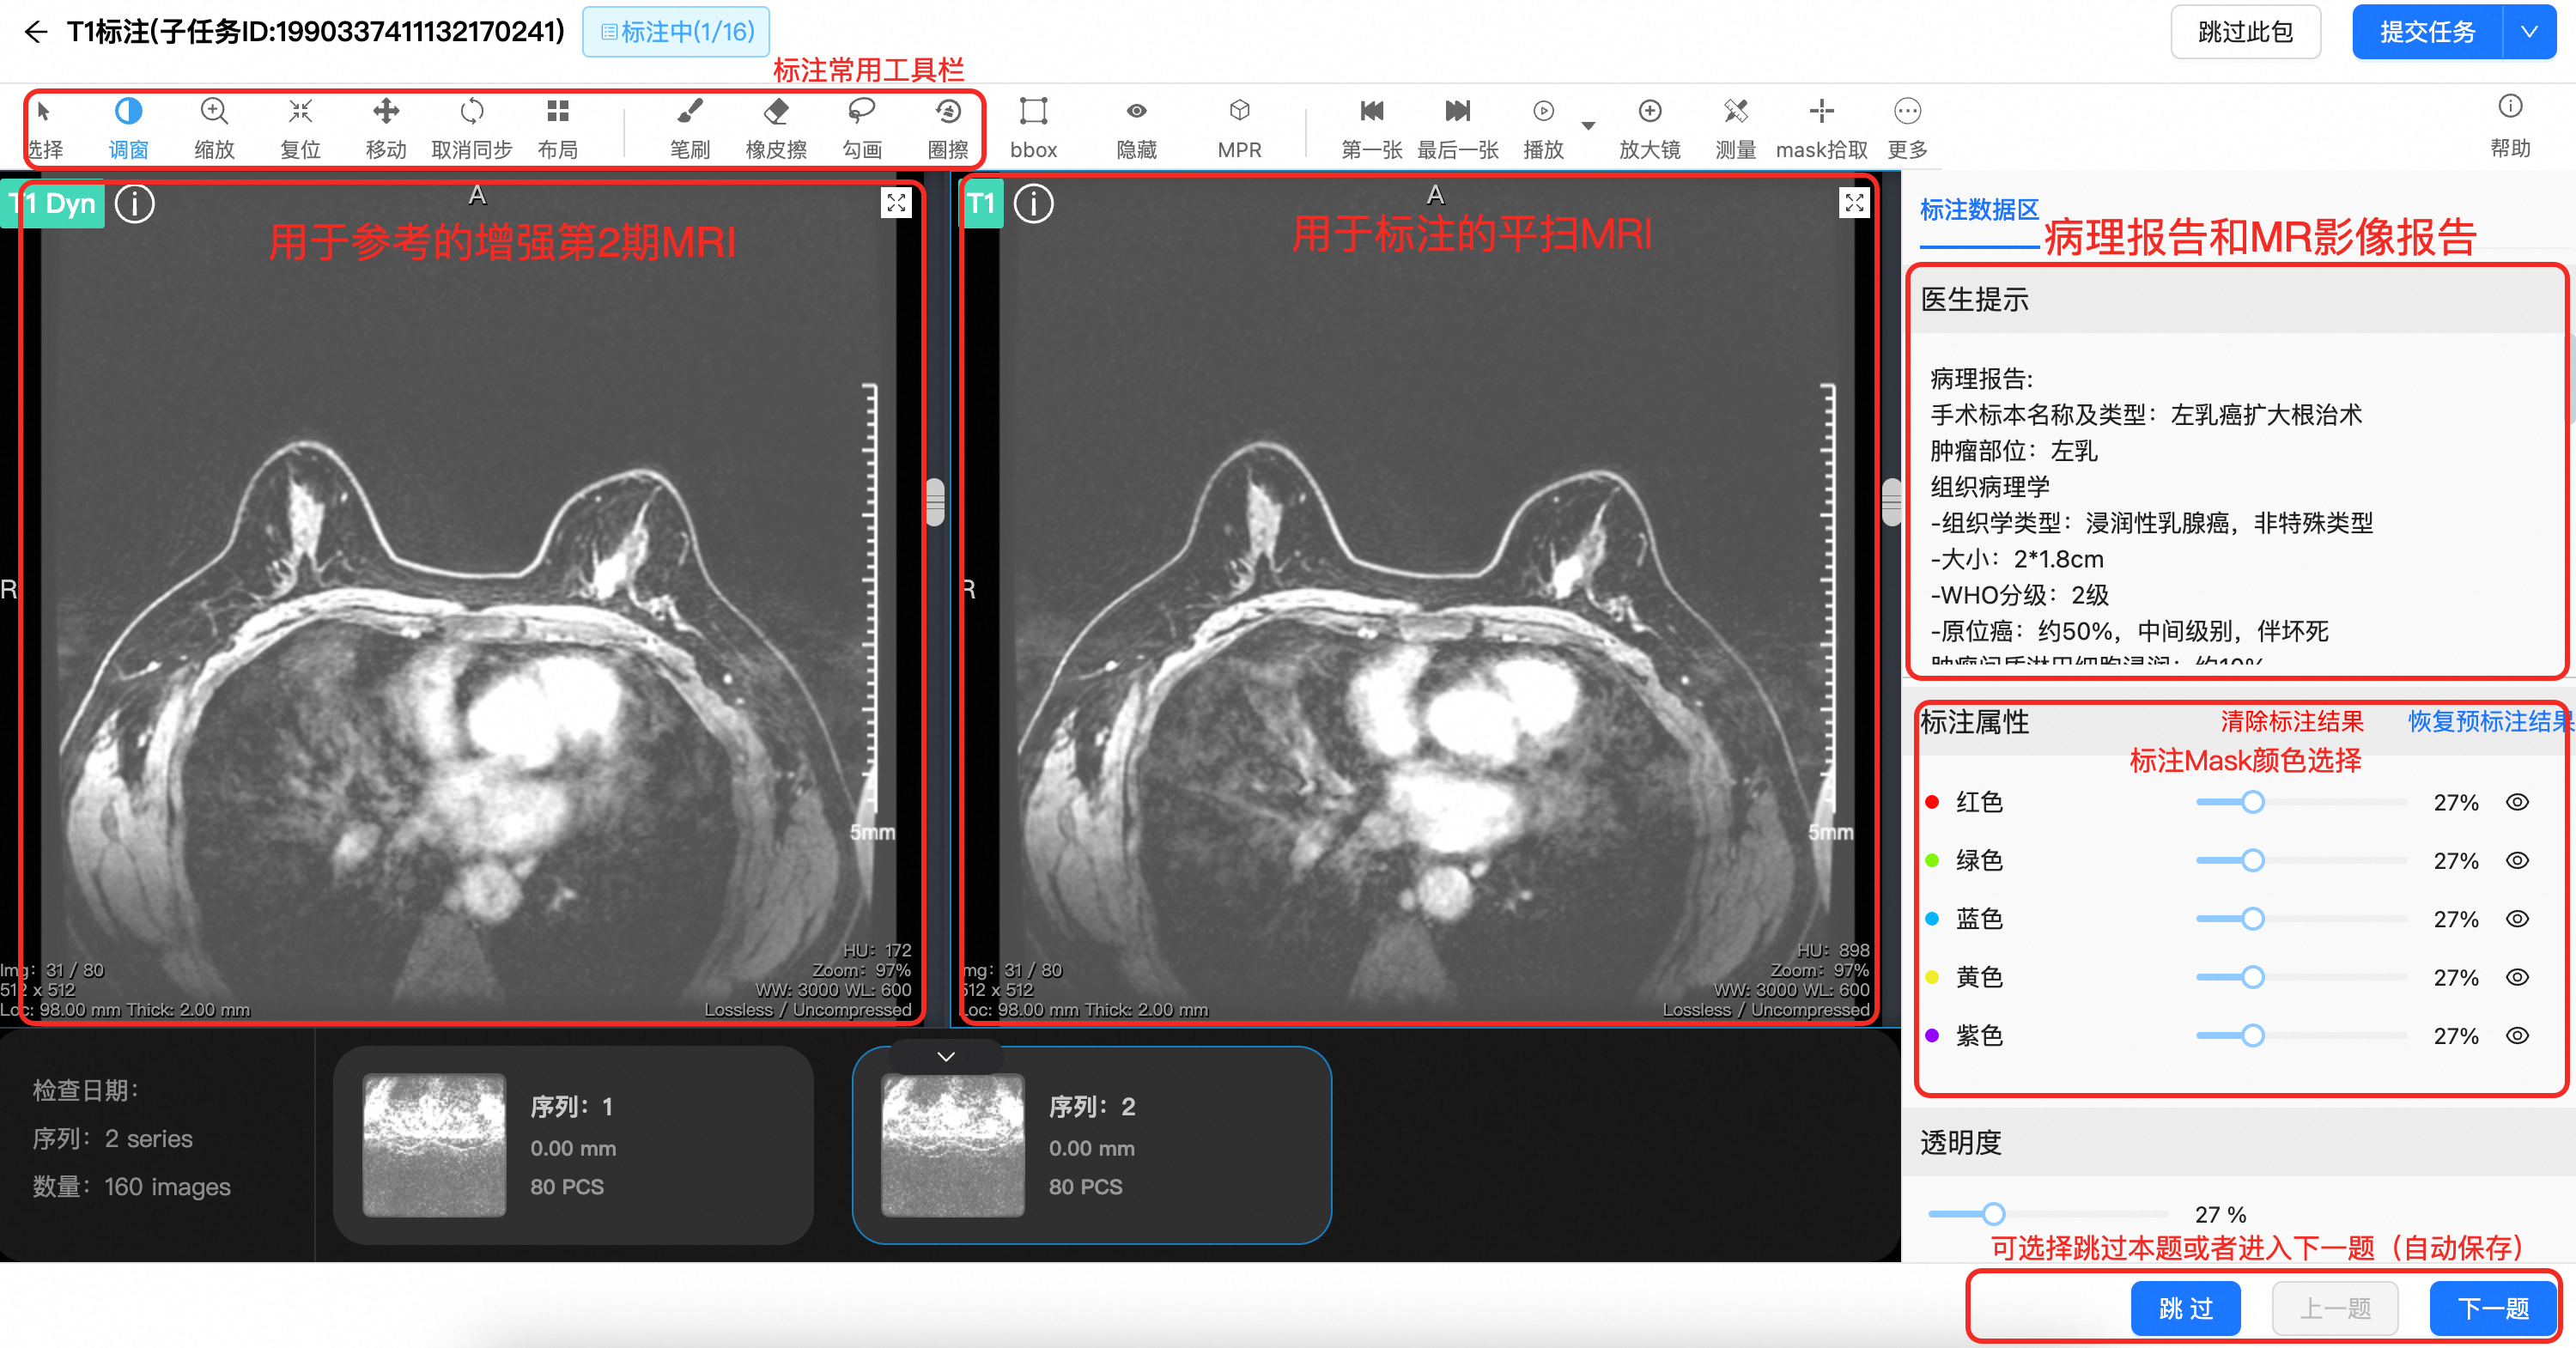

LangData智能标注平台

全流程AI辅助标注系统,大幅提升标注效率,降低标注成本,支持多类型数据标注与管理

长沙朗慧信息科技有限公司正式发布其旗舰产品——朗慧智能医学AI标注平台。该平台针对湖南乃至全国医疗AI行业的数据标注瓶颈,创新性地提出“AI+专家协同”工作模式与“国家级安全合规”保障体系。通过将AI预标注与专家复核相结合,平台将标注效率提升10倍,同时确保数据质量与安全。朗慧科技致力于通过此平台,为长沙、湖南及华中地区的智慧医疗发展提供核心数据动力。